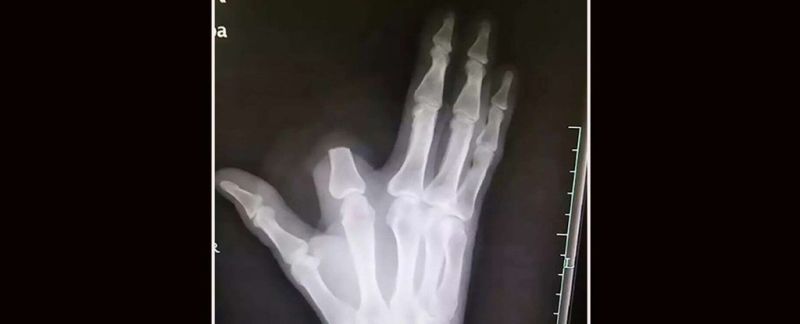

Un niño de 7 años acude al hospital con la mandíbula inflamada. Le extraen más de 500 dientes de la boca

Principios del pasado mes de julio. Al hospital Saveetha Dental College en Chennai, India, llega un pequeño de siete años con dolores y gran hinchazón en la mandíbula inferior derecha. Cuando termina la jornada los doctores no daban crédito. Le habían extraído al niño más de 500 dientes de la boca.